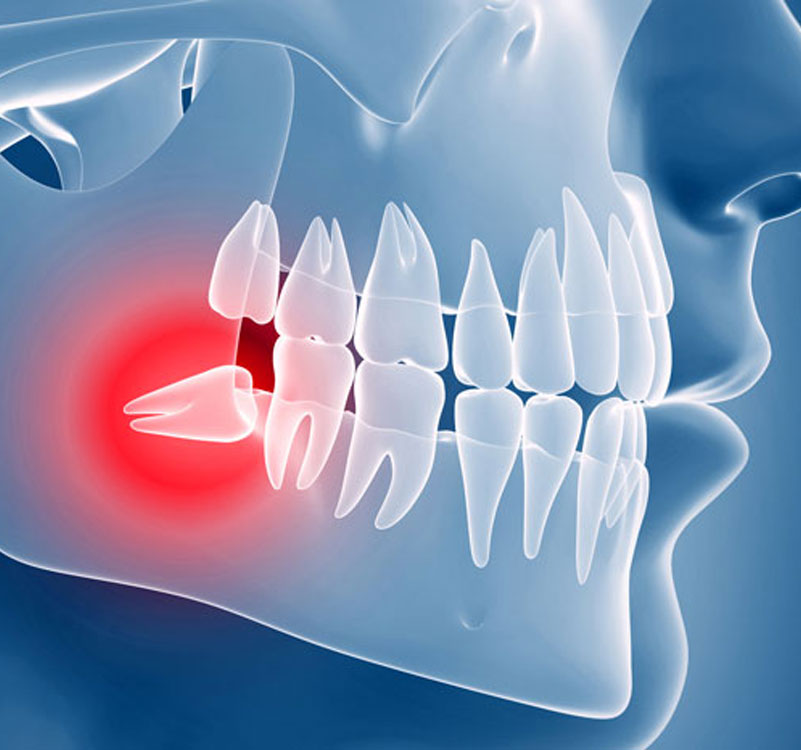

Chirurgia dei denti inclusi

I denti che più frequentemente sono soggetti a disodontiasi sono i terzi molari (molari del giudizio) e i canini (prevalentemente superiori). L'estrazione di questi denti richiede esperienza e particolare attenzione a causa della loro vicinanza (terzi molari inferiori) con parti anatomiche importanti, che se danneggiate possono portare a parestesie temporanee o permanenti fino all'anestesie del labbro inferiore. I molari del giudizio inferiori possono trovarsi in arcata come gli altri denti, possono essere semi­inclusi e quindi solo parzialmente coperti dalla gengiva o totalmente inclusi (al di sotto della gengiva o addirittura completamente all'interno dell'osso).

Oltre alla posizione verticale anche l'inclinazione può portare ad ulteriori difficoltà nell'estrazione. Grazie alla TC Cone Beam possiamo conoscere con la massima precisione la posizione tridimensionale del dente rispetto alle strutture nervose garantendoci una maggior sicurezza nelle procedure chirurgiche.

I canini superiori inclusi sono spesso recuperabili e possono essere riportati in arcata con un approccio combinato sia chirurgico che ortodontico. Come per la chirurgia rigenerativa nel nostro studio rispettiamo i massimi standard d'igiene e operativi anche nei casi di estrazioni di terzi molari o altri elementi inclusi. Estrazioni di denti inclusi vengono effettuate per motivi terapeutici (anche preventivi), protesici o ortodontici.